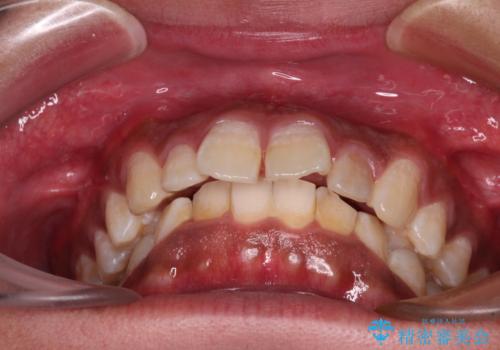

- 深く咬みこみ、前に飛び出した上顎前歯を気にして来院された患者様です。

口元の突出感はあまりありませんでしたが、上顎歯列が全体的に前方にあり、更には下顎歯列が深く咬みこんでいるために、上顎前歯が前方に突出している状態でした。